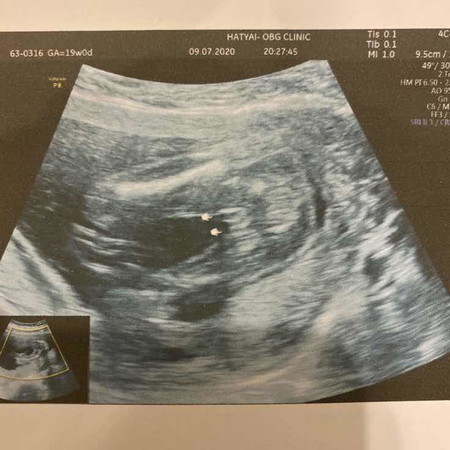

ช่วยคอนเฟิร์มหน่อยค่ะ สาวน้อยหรือหนุ่มน้อย 😅

น้องอายุ19สัปดาห์แล้วน๊า 😊

ผู้หญิงค่ะ เหมือนบ้านนี้เลย รูปซ้ายมีสองจุดเหมือนกัน

น่าจะผู้ชายนะคะ เพราะคล้ายกันเลย 😅

กลีบมาขนาดนี้ลูกสาวแน่นอนค่ะ

น่าจะสาวน้อยค่ะ

เหมือนจะผญ.นะคะ